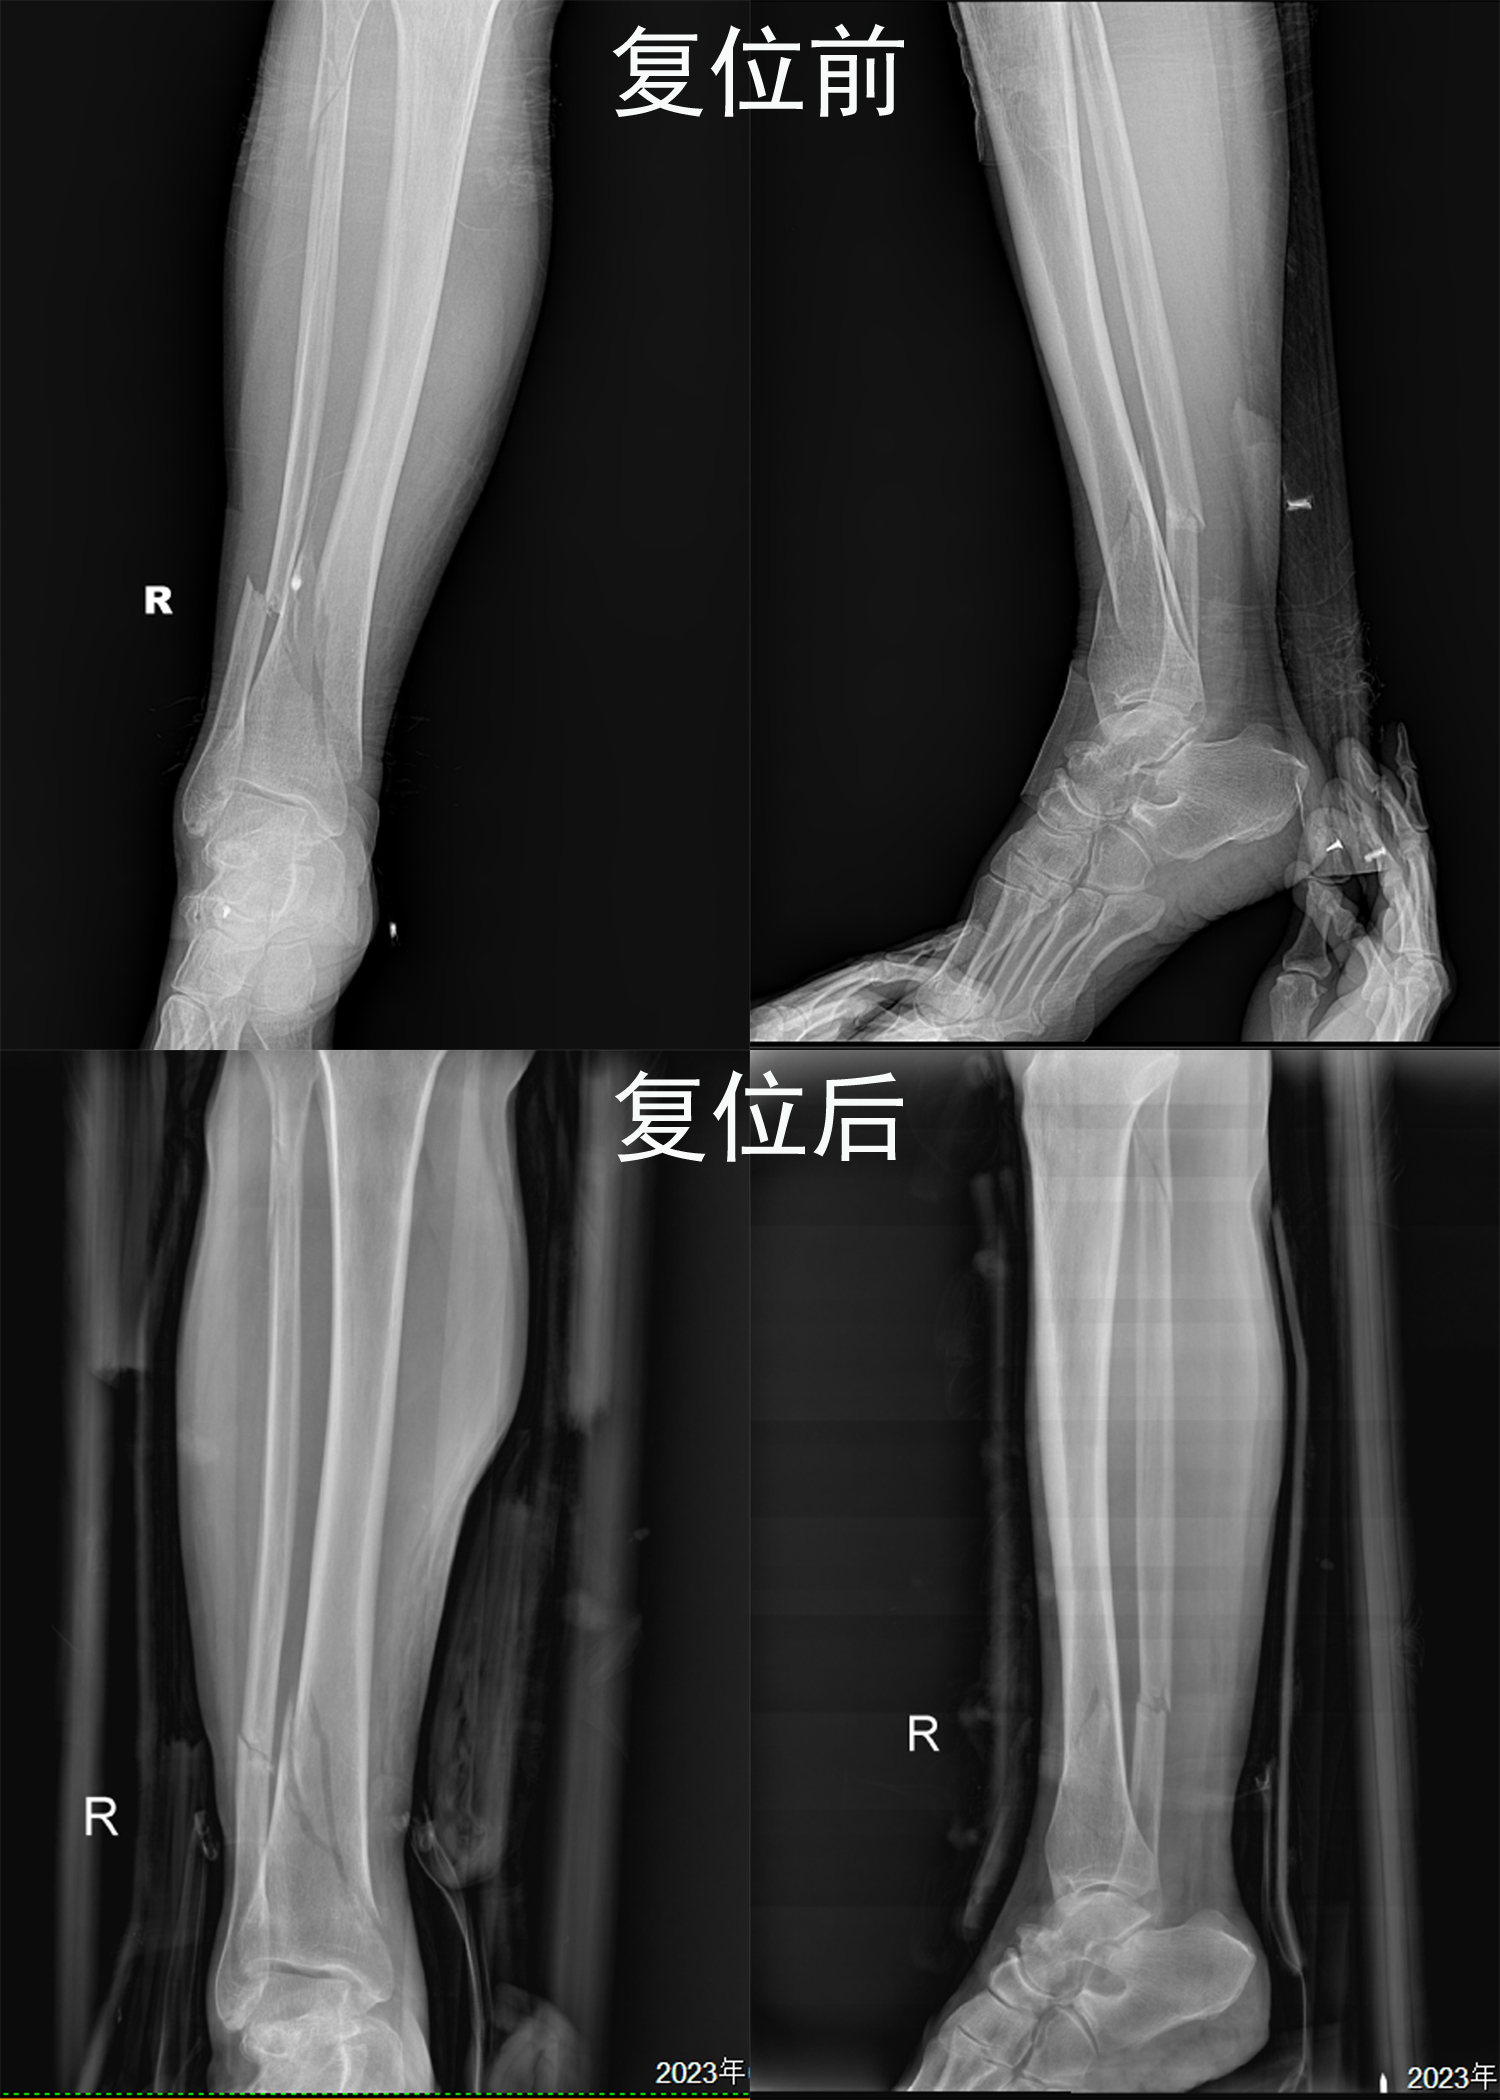

梁氏正骨-梁俊超正骨案例